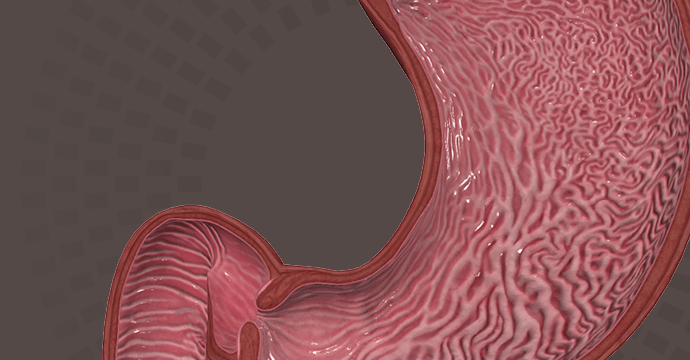

Take your understanding of human anatomy to the next level. Our comprehensive resources combine detailed information and stunning illustrations!

Enhance your studies for a truly dynamic learning experience. Explore interactive anatomy models from Complete Anatomy. Start mastering anatomy today with our free anatomy flashcards designed for quick review on the go.